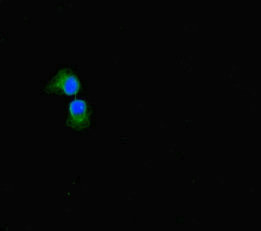

Immunofluorescent analysis of A549 cells using CSB-PA814217LA01HU at dilution of 1:100 and Alexa Fluor 488-congugated AffiniPure Goat Anti-Rabbit IgG(H+L)